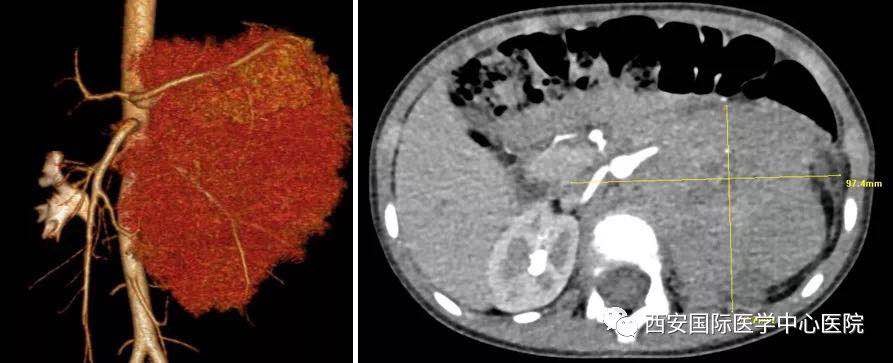

入院后,楊增悅主任仔細詢問病史、查閱影像學資料,第一時間為依依安排骨髓穿刺活檢,最終確診為:腹膜后神經母細胞瘤(Ⅳ期/L2)。CT顯示腫瘤巨大,侵及腹主動脈、腹腔干、腸系膜上動脈、雙腎動脈、腸系膜下動脈、下腔靜脈、雙腎靜脈、左腎及腎上腺、胰十二指腸、脾臟、結腸脾曲;腹膜后多發淋巴結轉移、骨轉移。骨穿病檢示:神經母細胞瘤骨髓轉移,腫瘤細胞占90.5%。經過科室團隊討論后決定,先行新輔助化療后再進行手術治療。

經6個周期的化療后,依依的骨髓腫瘤細胞由90.5%轉陰。

經多學科會診討論,泌尿外科專家團隊決定為依依行腹膜后神經母細胞瘤切除術。一切準備工作就緒,7月20日,在麻醉手術中心柴偉主任及其團隊的有力保障下,泌尿外科楊增悅教授主持指導,舒濤、王東,陳勇等協助完成。手術過程順利,術后患兒生命體征平穩,已返回泌尿外科普通病區進一步康復。